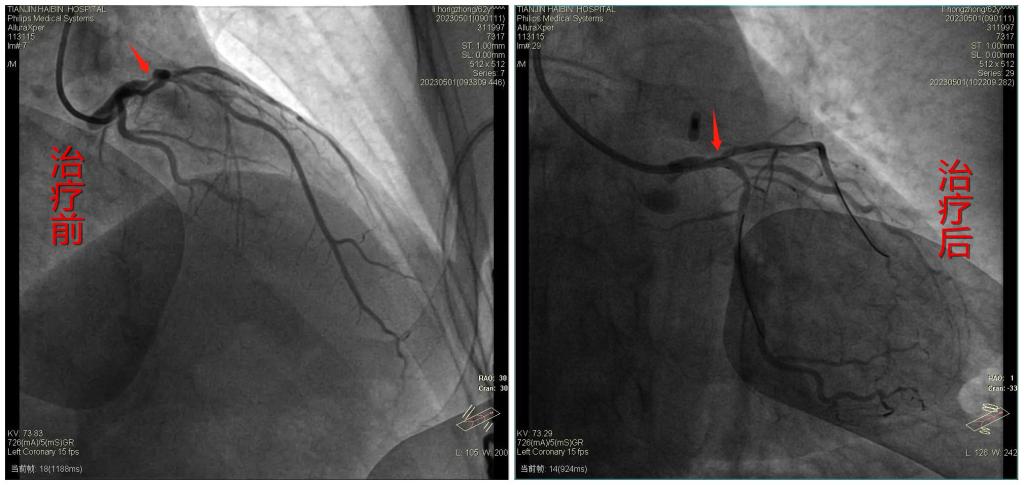

造影提示左主干末端狭窄95%,左主干与前降支直径跨度大,团队医生反复推演,决定先行球囊扩张,若病变为软斑块,预扩张理想,尝试药物球囊扩张,必要时V支架术式,双支架植入补救。手术方案拟定,一切准备就绪,手术如期进行。导丝在大夫手中灵活游走,像长了眼睛的探头,很快到达病变部位,医生麻利的在病变处进行球囊低压力预扩张,复查造影提示病变处预扩张效果理想。影像下观察患者情况比想象的要乐观,内膜光滑,无内膜坍塌及夹层形成,适合药物球囊术式。按照预定方案,大夫们立即在左主干至前降支以贝朗3.0*15mm药物球囊扩张术。穿刺、造影、球囊扩张等操作一气呵成,复查造影残余狭窄小于30%,无内膜撕裂及夹层形成,前降支及回旋支开口均未受影响,血运重建成功,TIMI血流Ⅲ级。